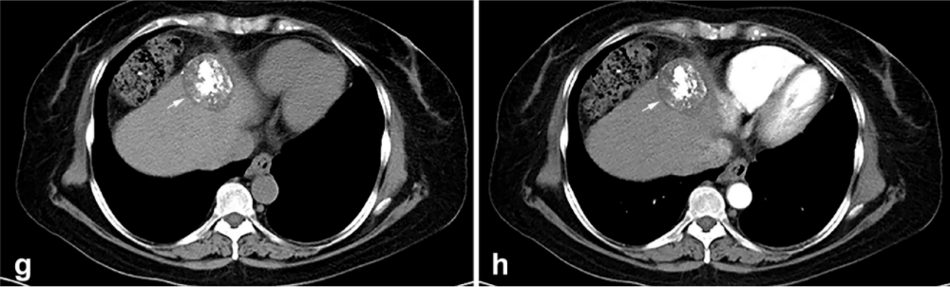

背景:由于一些原因,位于膈肌附近的腫瘤的熱消融在技術(shù)上具有挑戰(zhàn)性。首先,術(shù)中計(jì)算機(jī)掃描和超聲檢查無(wú)法清晰顯示射頻消融/微波消融切緣。第二,消融過(guò)程中不利的針?lè)植己瓦^(guò)熱可能導(dǎo)致肝包膜破裂,并對(duì)膈、肺和心臟造成嚴(yán)重?fù)p傷。第三,即使使用人工腹水,仍有9~22%的患者因肝周粘連或腫瘤位置靠近肝表面而導(dǎo)致膈肌熱損傷。冷凍消融可能是毗鄰膈肌的HCC的一種有前途的治療方法,因?yàn)樵谙谶^(guò)程中使用CT和US可以很好地顯示腫瘤邊緣。盡管一些研究評(píng)估了在高危區(qū)域使用冷凍消融治療HCC,但很少有研究針對(duì)膈肌臨近區(qū)域。

① 術(shù)后 1 月腫瘤治療反應(yīng):冷凍消融術(shù)后一個(gè)月腫瘤疾病控制率達(dá)95.9%。

③ 總生存曲線和局部腫瘤進(jìn)展曲線:冷凍消融后中位生存時(shí)間為 27.3 個(gè)月,中位局部腫瘤進(jìn)展時(shí)間為 20.9 個(gè)月。